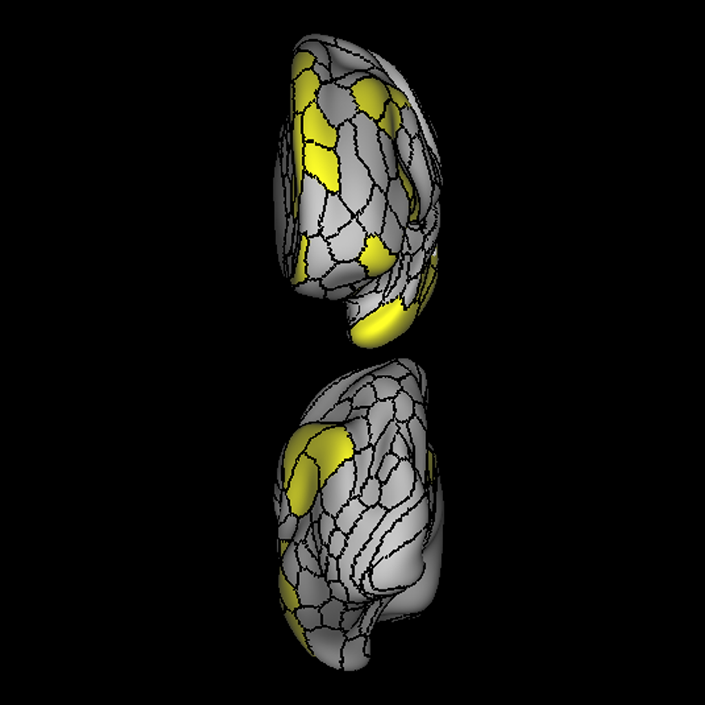

ᐅ SummaryArea 44: part of the inferior frontal gyrus of the lateral frontal lobe. Translates abstract and intentional information in the prefrontal cortex to more detailed representations to help guide the production of verbal and manual actions. In addition to its known association with Broca's area, is sometimes represented as part of Broca's complex ᐅ Where is it?Area 44 is at the posterior most part of the inferior frontal gyrus. It is the anterior bank of pars opercularis of the IFG. ᐅ What are its borders?Area 44 borders area 45 anteriorly and area 6r posteriorly. Area 8C is its medial border and its inferior border is wedged between then upper borders of Areas 6R and 6V. Its superior edge borders IFSp and IFJa. Its opercular surface is FOP4. ᐅ What are its functional connections?Area 44 demonstrates functional connectivity to areas SFL, IFSp, IFJa, 45, 47s, 47L, 9a, 9m, 8AV, 8BL and 8C in the dorsolateral frontal lobe, area 8BM in the medial frontal lobe, area 55b in the premotor areas, areas FOP5, AVI and PSL in the insula- opercular region, areas TGd, STSdp and STSvp in the temporal lobe, areas PFm, and PGi in the inferior parietal lobe, and no areas in the medial parietal lobe. ᐅ What are its white matter connections?Area 44 is structurally connected to the arcuate/SLF and the FAT. Connections with the arcuate/SLF project posteriorly and wrap around the Sylvian fissure to the middle temporal gyrus to end at TE1a and TE1m. There are also projections from the arcuate/SLF before it terminates to parcellations A5 and STSdp. The majority of the inferior connections of the frontal aslant tract end at 44, the tract is connected superiorly to superior frontal gyrus parcellations SFL, 6ma and s6-8. Local short association bundles are connected with 45 and 8C. White matter tracts from 44 in the right hemisphere have less consistent connections with the arcuate/SLF. ᐅ What is known about its function?Area 44 translates abstract and intentional information in the prefrontal cortex to more detailed representations to help guide the production of verbal and manual actions. Area 44, in addition to its known association with Broca's area, is sometimes represented as part of "Broca's complex", including Brodmann Areas 45, 46, 47 and the mesial supplementary motor area of 6, which contribute to a frontal-subcortical circuit. The right pars opercularis has also been implicated in cognitive inhibition in the overall context of working memory. |

A: lateral-medial

B: anterior-posterior

C: superior-inferior

DTI image |